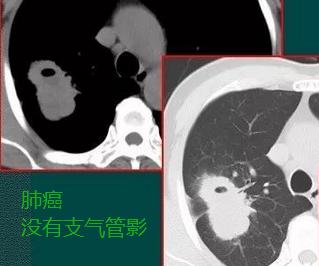

也许读者朋友对上面的文字内容不够理解,我们再看几张类似的肺癌的肿块图:

肿块边缘清晰,没有云雾状影,空洞呈偏心性,空洞壁没有支气管,病理证实为肺腺癌